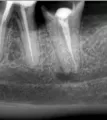

Зуб и в правду следует удалять. На фотоснимке видна перфорация корня инструментом. Никакое консервативное лечение не даст уверенную гарантию на этот зуб. Так что зуб рекомендовано удалять.